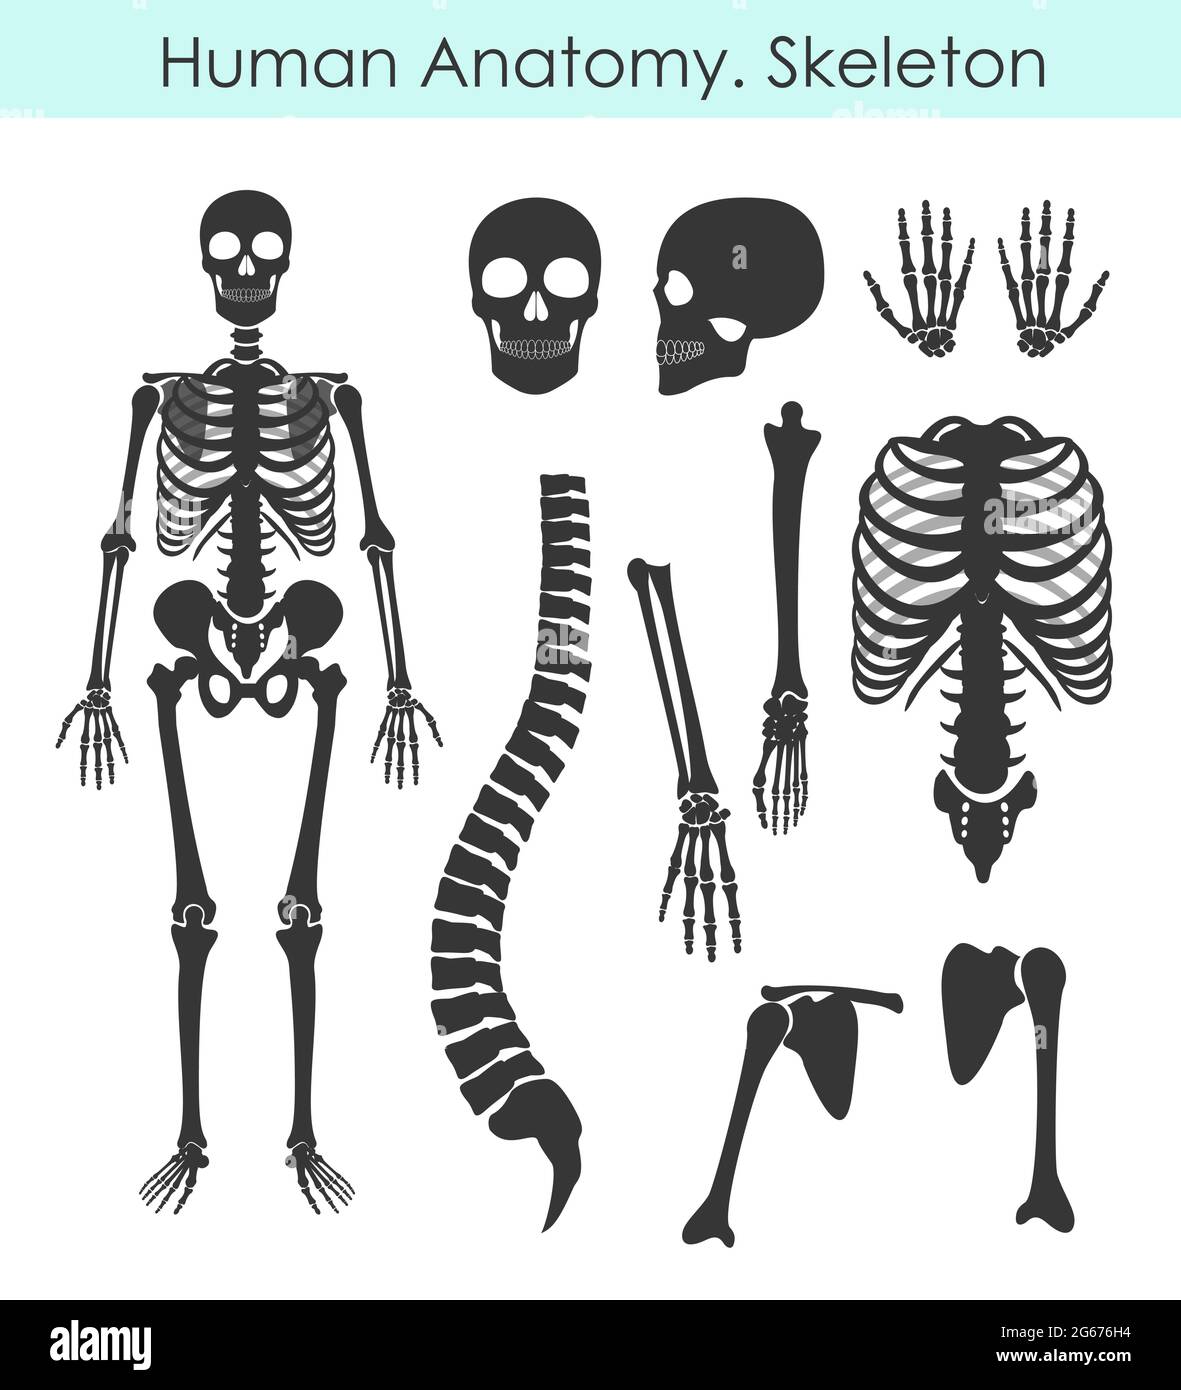

RF2G676H4–Ensemble d'illustrations vectorielles du squelette humain. Collection de silhouettes All Human Bones de style plat isolée sur fond blanc.